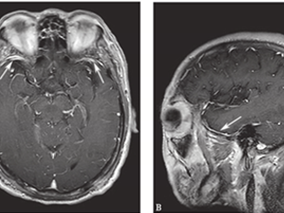

1小时条评论【病例资料】 患者,男性,42岁。因发作性右眼闪光感3次,进行性言语欠清3个月于2011年5月23日收入院。 现病史:患者于2011年2月2日无明显诱因发作4次右眼外侧视野闪光感,闪光呈红、黄、蓝三色,持续1分钟左右自行缓解。2月12日出现言语欠流利,就诊于北京某医院...